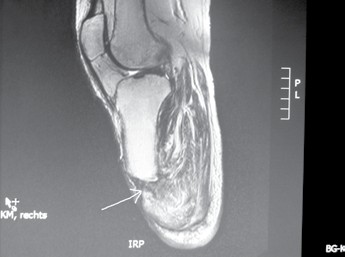

- In vielen Fällen wird schon unmittelbar postoperativ zur Linerversorgung mit oder ohne Pin gegriffen. Dabei sollte der Liner mit Pin wegen seiner negativen Folgen für den Stumpf bis auf ganz wenige Ausnahmen heute für den Unterschenkelstumpf obsolet sein. Aber auch jeder andere Liner ist besonders im Rahmen der Versorgung eines Unterschenkel- oder Syme-Stumpfes in Abhängigkeit von der Grundkrankheit und der damit in Zusammenhang stehenden Konsolidierungszeit bis zur 8. bzw. 12. postoperativen Woche nicht zu empfehlen. Sehr viele Patienten können den Liner nicht von dorsal nach ventral anziehen, sonrdern rollen ihn von ventral nach dorsal auf und reißen dabei die „feinen“ Nähte aus, die die Verbindung zwischen Muskulatur und z. B. Periost darstellen. Die Folge: Das Operationsresultat ist zunichtegemacht, und es entsteht wiederum ein Weichteilüberschuss, den man – z. B. bei einer Revision – gerade beseitigt hatte (Abb. 6a–h).